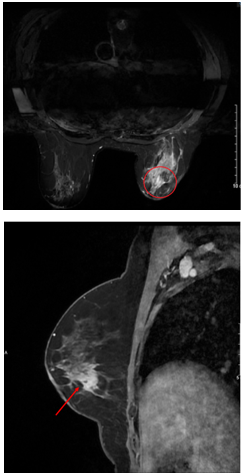

MRI động học tuyến vú: Hiện không thấy tổn thương ngấm thuốc vú phải - đáp ứng hoàn toàn sau điều trị. Hiện không thấy tổn thương nghi ngờ ác tính trên phim cộng hưởng từ tuyến vú trái (BIRADS 1). Hạch nách phải (không thay đổi so với phim cũ).

Hình 5.

Hình ảnh MRI u vú trước (bên trái) và sau điều trị (bên phải): Khối ngấm thuốc ¼ dưới ngoài vú phải trên phim MRI trước điều trị hiện không thấy trên phim MRI sau điều trị.